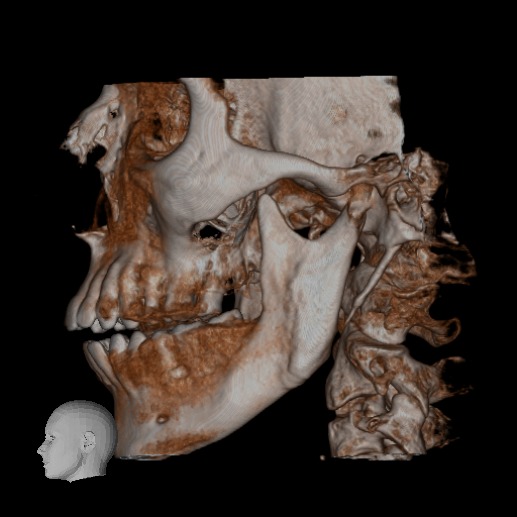

El Centro Radiológico Diagnóstico Oral 3D, es una empresa antioqueña que ofrece a sus pacientes desde el año 2009, tecnología de vanguardia en radiografías tridimensionales con calidad fotográfica. Las posibilidades para mejorar la eficacia en los diagnósticos bucales son evidentes, también lo son las posibilidades de manipulación de imagen. El sistema de imágenes en 3D ofrece detalles sin precedentes, convirtiéndola en la opción idónea para la mayoría de aplicaciones odontológicas, incluyendo implantes, tratamiento de conductos, ortodoncia, odontopediatría, periodoncia y cirugía

El mayor beneficiado con el uso de esta tecnología es el paciente, el cual podrá ser evaluado en todas sus dimensiones con una baja dosis de radiación, con un costo accesible y sin contaminar  el medio ambiente. Dependiendo de la necesidad del paciente, hay varios tipos de tomografías y los especialistas en el área odontológica hacen uso de ellas según su especialidad.

Evaluación de patologías dentales y maxilofaciales

Implantología dental